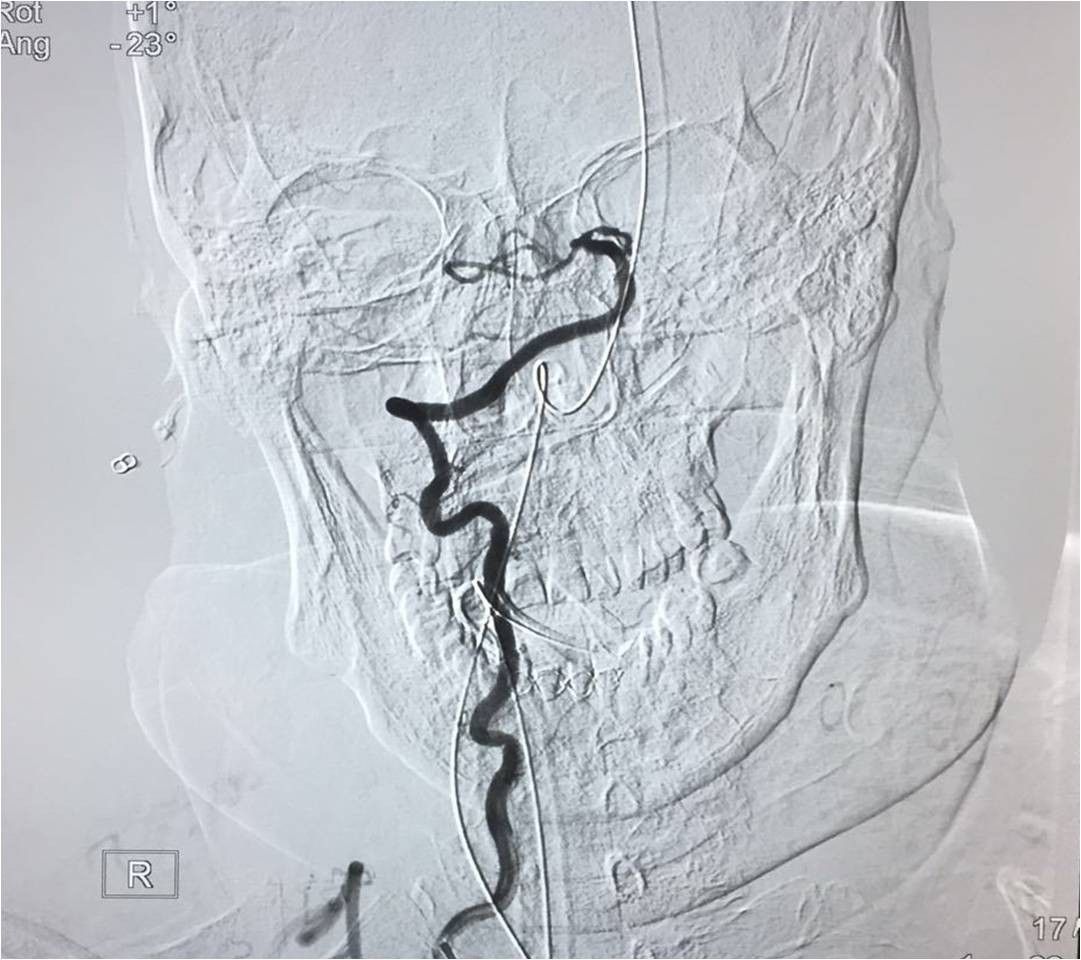

▼微导管定位